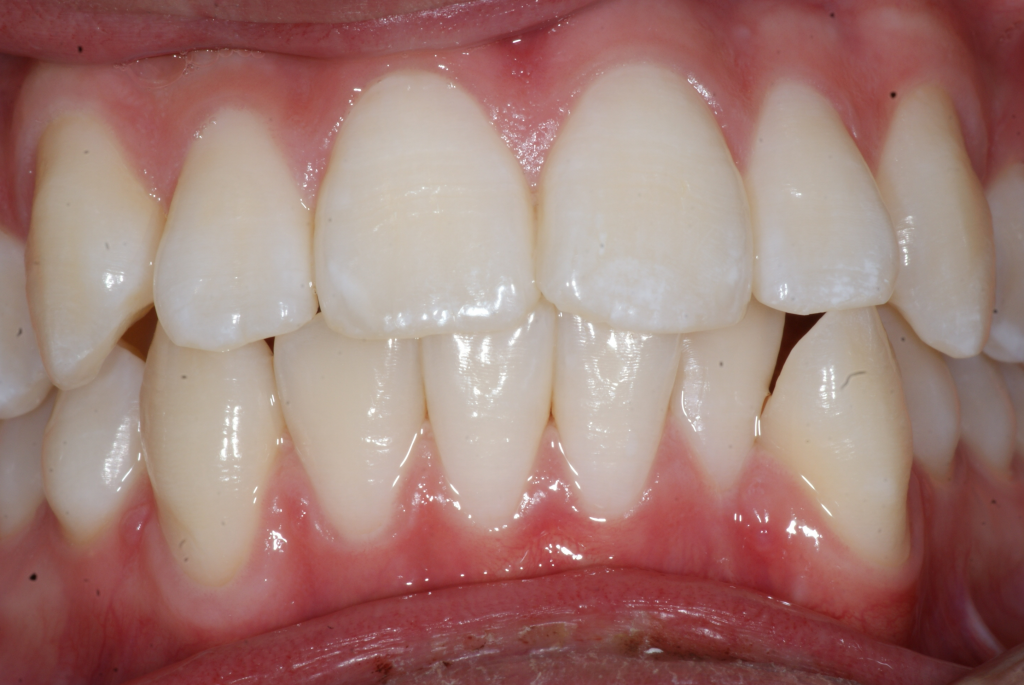

Correction d’une malocclusion de type bimax, canine #33 ectopique et chevauchement léger aux 2 arcades.  Des appareils fixes (broches) et extraction de 4 prémolaires furent nécessaires pour améliorer ce sourire.  Traitement chez un jeune adulte, réalisé en 28 mois.